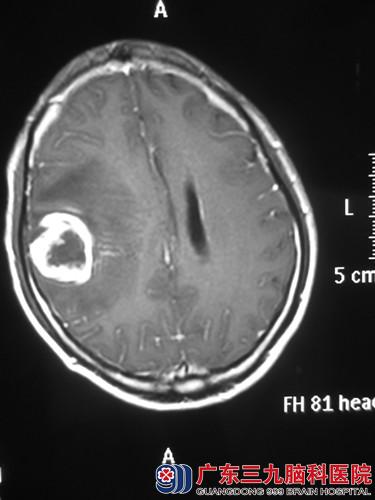

经头颅MR检查提示右额叶占位,直径约3cm。完善相关检查后,由鲁明主任主刀,术前导航计划,显微镜下见肿瘤呈灰白色,血供丰富,术中再次导航定位肿瘤位置,电生理监测避开脑功能区,唤醒患者,在患者语言及肢体运动配合下,连同受侵犯脑皮层一并全切肿瘤,手术顺利结束。术后经过专科治疗护理,王先生语言、肢体活动正常,未出现功能障碍。术后病理结果:胶质瘤(WHO IV级)。

术前